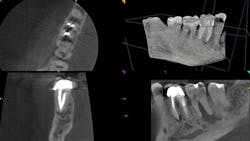

Radiolucency seen on the first molar, and the second molar demonstrates major bone loss in furcation due to a fractured root. The axial view depicts a resorptive defect along the actual fracture line.

The buccal and palatal plates of bone are intact here, but there is tremendous infection in the furcation.